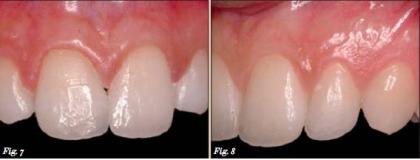

1/3 phía rìa cắn của răng cửa bên hàm trên được tái tạo tương tự như trên để đạt được đặc điểm thẩm mỹ và chức năng hợp lí (Hình 7-8).

Hình 7-8: răng cửa bên hàm trên được tái tạo với các bước tương tự.